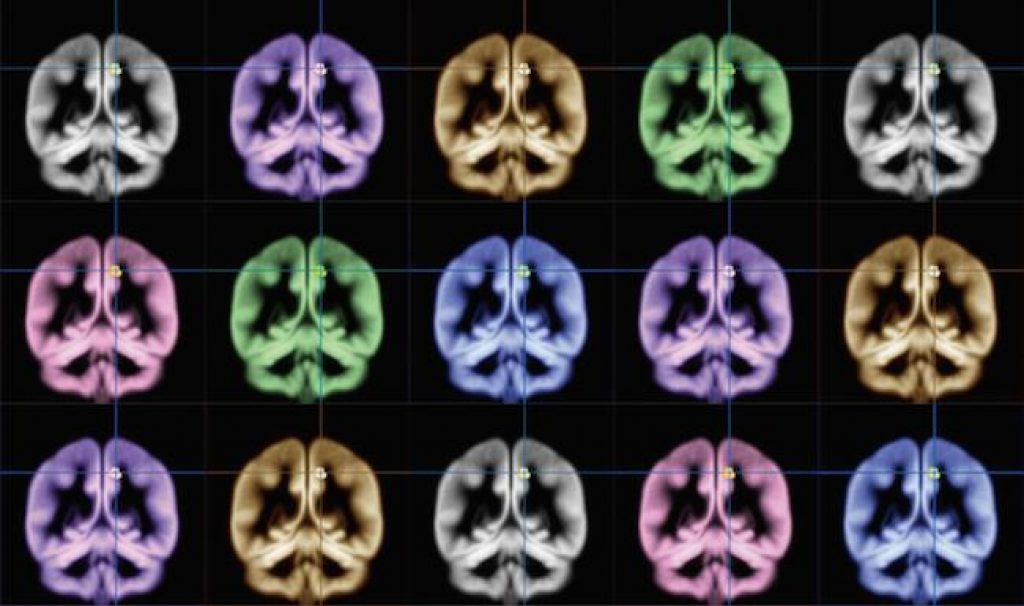

Sato and his team scanned the brains of research participants with an MRI. The participants then took a survey that asked how happy they were generally, how intensely they felt emotions, and how satisfied they were with their lives.